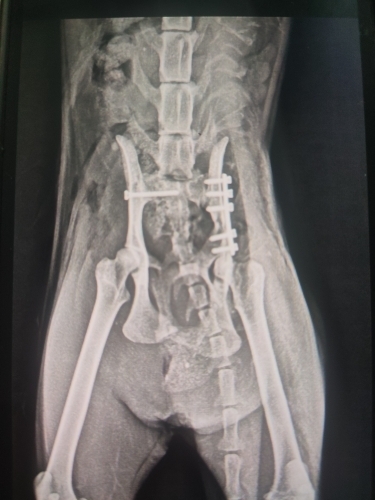

29 Ocak’ta mahallemizde baktığımız sokak kedimize bir araç çarptı. Onu arka ayaklarını sürürken bulduk. Ertesi gün acil olarak ameliyata alındı; operasyon başarılı geçti ve bacağı plakla sabitlendi. Ancak sinir hasarı olduğu söylendi. Bu süreçte klinikte, kafeste kaldı.

Geçen hafta kontrol amaçlı yeniden röntgen çekildi. Ne yazık ki plak gevşemiş ve kaymış; bu nedenle revizyon ameliyatına alındı. Ameliyat teknik olarak iyi geçti fakat bu kez çok kötü bir haber aldık: Kedimiz hamileymiş.

Mevcut durumda arka bacağının birinin ampute edilmesi gerekecek ve doğum sezaryenle yapılacak. Planlanan süreç, önce sezaryen, ardından amputasyon şeklinde ilerleyecek tek narkozla olması açısından.